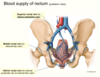

The two pelvid floor muscles: 1: _______ and 2: _________.

Muscle 1 can be split into 3: _________ , and 4: ________.

4: has different parts called _________ and ___________ / ____________.

1: Levator ani, 2: coccygeus (ischiococcygeus).

3: Illiococygeus, 4: pubococygeus.

called the puborectalis (not connected to the median raphe) and the pubovaginalis (which forms the sphincter of the vagina) /puboprostatis (wraps around the prostate).

Pubococcygeus is separated further. Purple is the puborectalis, it does a turn around motion (doesn’t attach to median raphe), this helps with angulation between anus and rectum.

The part of the pubococcygeus part forms the pubovaginalis, this forms sphincter of vagina. In the males it goes around the prostate and is called the puboprostatis.